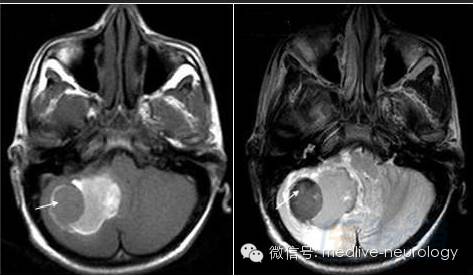

然后解决第三个问题,轻松一下,图来啦,让我们巩固一下今天学习的成果,均为先T1,后T2。

亚急性早期(3-7d): 脑桥